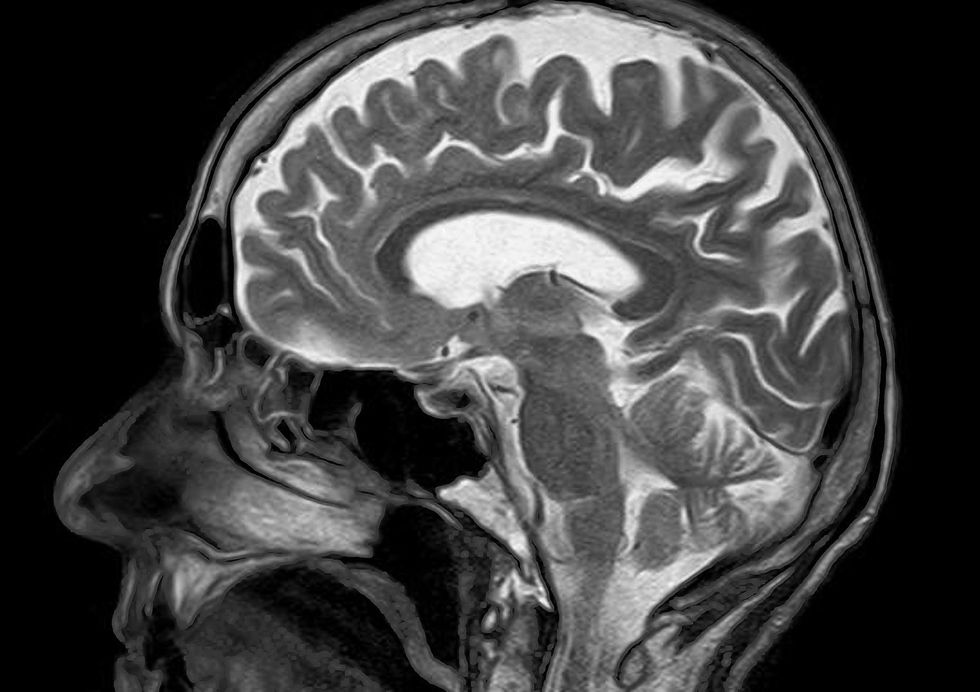

Now, though, the man has had two microchips placed in his motor cortex which controls movement. While his family had feared that he’d soon be unable to communicate, those fears have now been negated.

The chips register activity in the brain, and when there is an increase in activity a rising sound plays on a device. When there is a decrease, the computer plays a descending tone.

Researchers Ujwal Chaudhary and Niels Birbaumer published their findings in Nature Communications. They call the method neurofeedback, with the patient able to see their activity recorded in real time and learn to control it.